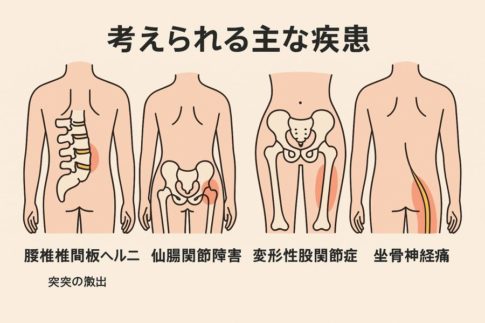

② 運動後に股関節が痛くなる主な原因(タイプ別)

・筋肉・腱の炎症(オーバーユース)

・鼠径部痛症候群(グロインペイン)

・股関節インピンジメント・関節唇損傷など(構造的要因)

・姿勢やフォームによる負担(反り腰・偏ったフォーム)

② 股関節 痛み 運動後に多い主な原因とは?

・筋肉・腱への負担(使いすぎ・オーバーユース)

・フォームや姿勢のクセによる影響

・股関節まわりの柔軟性・筋力バランスの低下